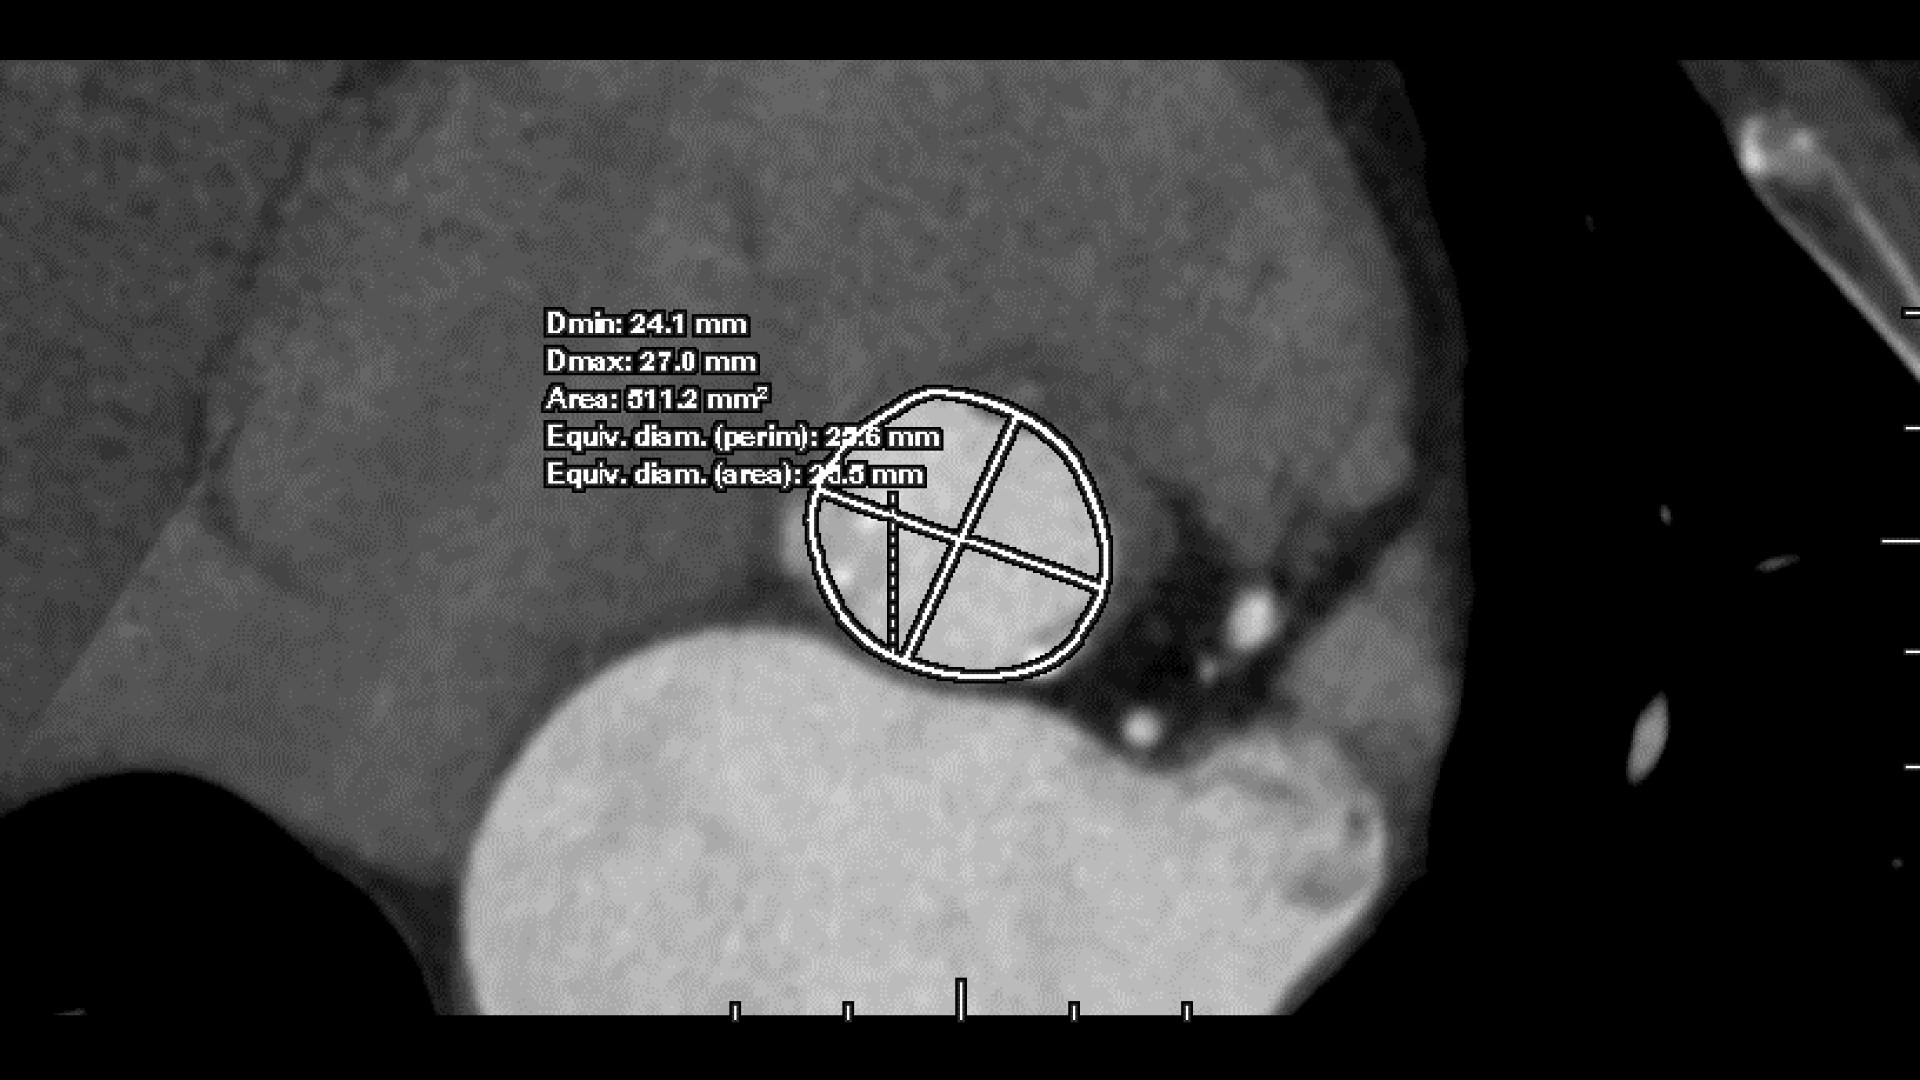

• Automated aortic segmentation and preliminary orientation to aortic annular plane

• 3-point deposit mode for precise refinement of annular plane

Annoni AD, Mancini ME, Carlicchi E, Belmonte M, Formenti A, Mushtaq S, Marchetti F, Cilia F, Baggiano A, Fusini L, Bonomi A, Gennari M, Montorsi P, Pepi M, Pontone G.

Pre-TAVI aortic annulus sizing: comparison between manual and semi-automated new generation software measurements in operators with different experience.

Br J Radiol. 2023 Sep;96(1149):20220733. doi: 10.1259/bjr.20220733. Epub 2023 Jul 26. PMID: 37449675; PMCID: PMC10461289.